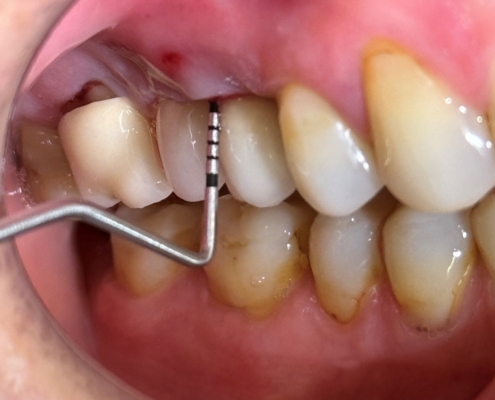

Periimplantitis je upalno patološko stanje koje zahvaća tkiva u neposrednoj okolini dentalnog implantata, pri čemu dolazi do upale periimplantatne sluznice i postupnog gubitka koštanog potpornog tkiva. Kliničke manifestacije periimplantitisa uključuju upalu, krvarenje pri sondiranju, supuraciju, povećanu dubinu sondiranja i gubitak kosti (Slika 1.). Upala mekih tkiva obično se otkriva krvarenjem pri sondiranju, dok se gubitak kosti prepoznaje na radiografskim snimkama kao ˝krater˝ oko implantata uz povećane dubine sondiranja (Slika 2.). Dubina sondiranja može ukazivati na ozbiljnost bolesti i korelira s gubitkom kosti, čija brzina varira među pacijentima (1). Periimplantitis se često razvija kod pacijenata s prethodnom anamnezom uznapredovalog parodontitisa, lošom kontrolom plaka te nedostatkom redovite terapije održavanja nakon implantološkog zahvata.